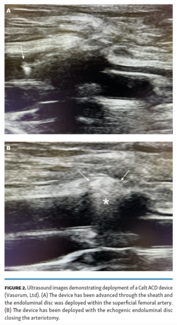

This article seeks to evaluate the effectiveness of the Celt ACD (Vasorum, Ltd) for the closure of antegrade superficial femoral artery access to treat ipsilateral lower-extremity arterial lesions.